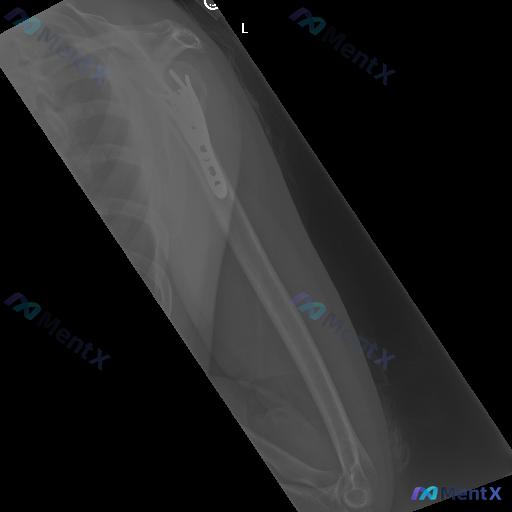

左侧肱骨近端术后X线:骨质密度不均,你会先往哪条线考虑?

整理到一份左侧肩部及上臂的X线正位影像资料,情况如下: - 既往史背景:左侧肱骨近端有手术内固定史 - 本次X线表现: 1. 肱骨近端外侧可见解剖型锁定钢板及多枚螺钉,位置看起来稳固,没有明显断裂、松动或移位 2. 肱骨头及大结节区域有骨质结构重塑表现,骨折线愈合良好 3. 盂肱关节、肩锁关节对位关...